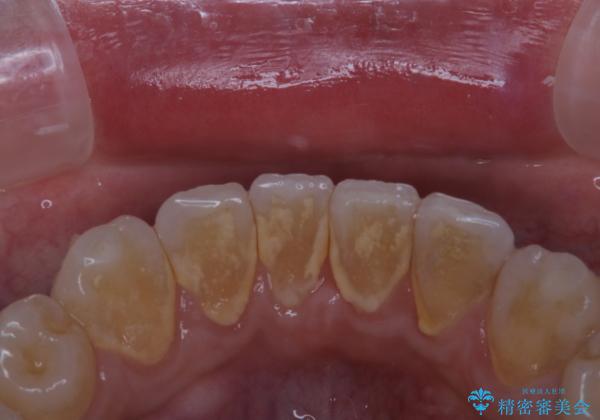

- インビザラインでのマウスピース矯正中の患者様です。

歯石による舌ざわりが気になるとのことでした。

PMTC30分コースを行いました。

プラークやバイオフィルムといった細菌などを放置すると歯石となります。歯石になってしまうと歯磨きでは取り除くことができないため、歯科医院にて専門的な機械や材料を使用してクリーニングを受ける必要があります。